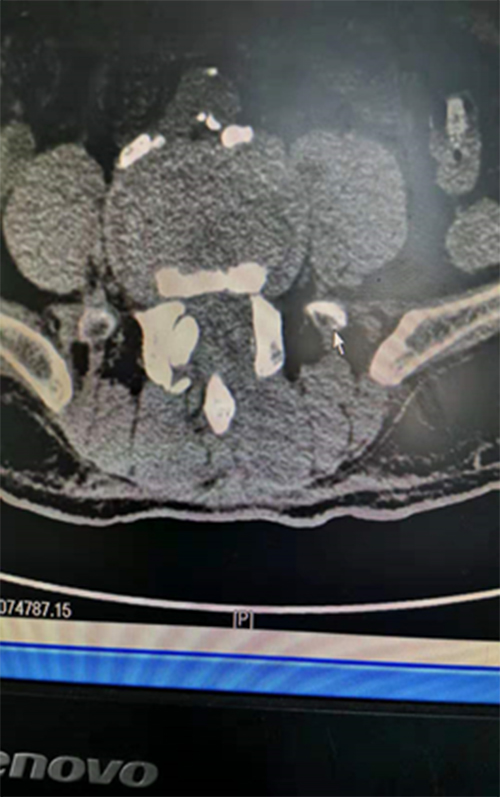

三、术后影像学表现